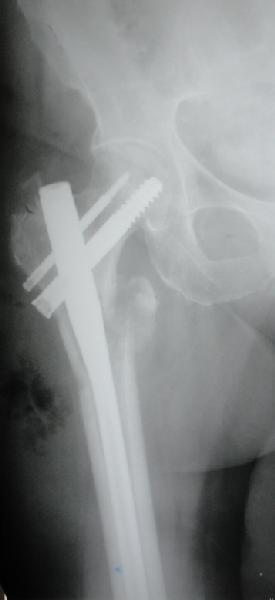

Фиксация * reversed obliquity* подвертельных переломов - дело непростое.

На мой взгляд, причиной телескопирования явилось несоответствие диаметра гамма нэйл с диаметром канала подвертельного отдела бедра: обратите внимание на величину протрузии шеечного винта и величину медиализации дистального фрагмента - они одинаковы, смещение или телескопирование фрагментов происходило до того момента, пока гамма нэйл не упёрся в медиальный кортекс и образовалось пространство между латеральным

кортексом и латеральной поверхностью гвоздя.

Диаметр гаммы в диафизарной части ~11 мм. А диаметр канала, тем более у пожилых с остеопорозом, может быть мм 15. Даже рассверливать обычно не приходится, после формирования широкого канала в вертельной области можно сразу толкать гвоздь, он влетает, как карандаш в стакан. Так что соответствия диаметров не бывает никогда. Однако представленная ситуация случается далеко не каждый раз. Если гвоздь в центральном отломке входит чуть медиальнее верхушки вертела, и идет вдоль передне-латеральной стенки центрального отломка, то все будет хорошо.

В приложении похожий пример, к счастью, пациентка появилась не после, а "за полчаса" до протрузии. Пересинтезировали с исправлением ошибок.